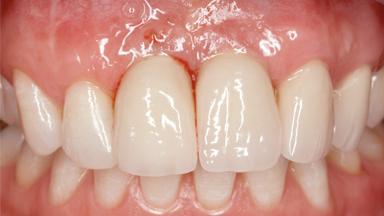

A 30-year-old woman was referred by her general dentist for evaluation of an esthetic complication related to previous implant treatment for congenitally missing maxillary lateral incisors. The patient’s chief complaint was the inadequate esthetic appearance of her smile. The case demonstrates the use of a combined approach to achieve optimal results. Two different flap designs - a tunnel technique and a coronally advanced flap - are employed based on the surgical objectives for the affected site.